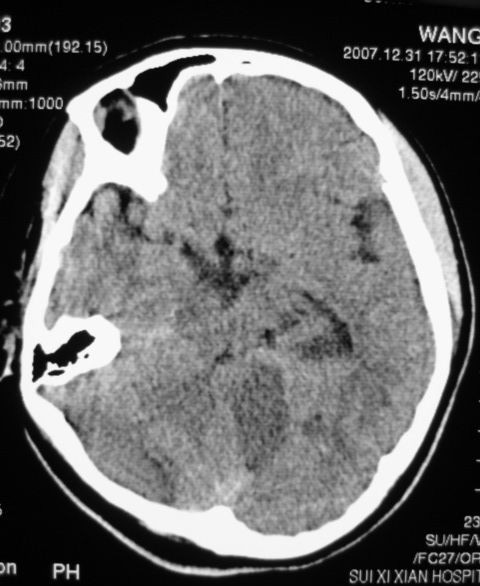

以下是引用zjzjr在2008-2-19 15:45:00的发言:[br]左侧小脑缺血性脑梗塞,基底节区脑梗塞,强烈建议血管造影,除外烟雾病。

以下是引用玉真在2008-2-19 17:46:00的发言:[br]多发性脑梗塞,不知病人是否有风心或先心病史